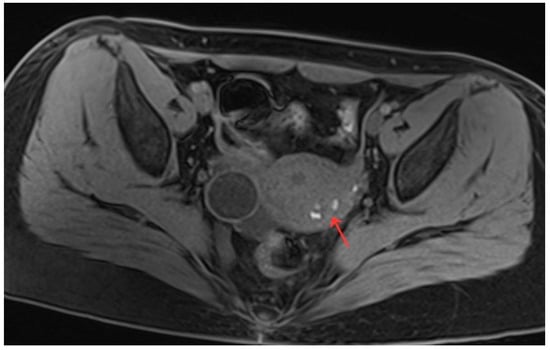

Figure 7.

Pelvic MRI shows lesions HIFU treatment (8th month) (red arrow).